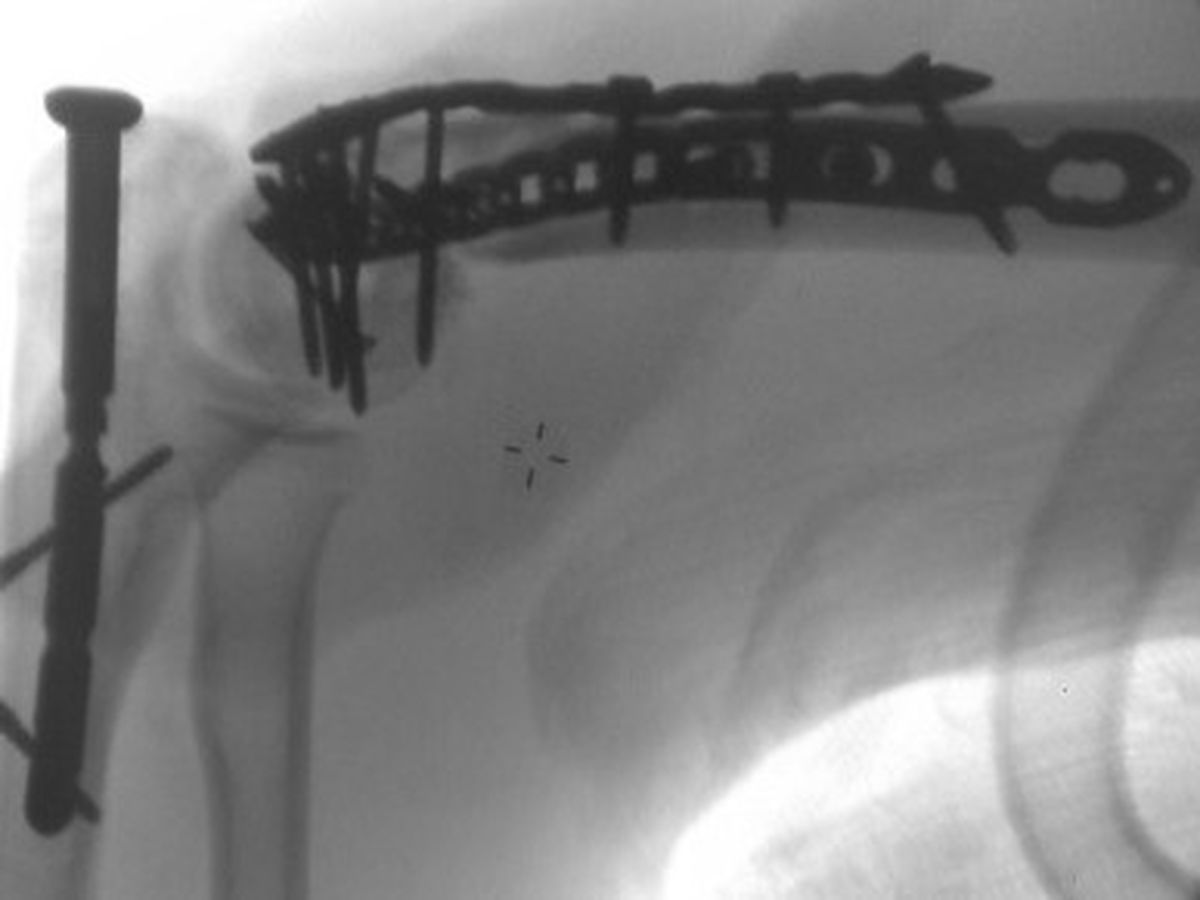

The attached picture is an x-ray of his arm post-surgery.

The ambulance rushed him to a hospital in Gibson City, which is where I went to go see him. The doctor there x-rayed his arm and said that is was broken in many different places. The doctor said that the bones were shattered and he was not confident enough to perform the surgery needed for it, and transferred Matt to the hospital in Urbana. They tried to get his pain under control until the doctor came and looked at his arm in the morning. That morning, another surgeon turned down performing the surgery because the damage was so extensive.

Matt was attacked on a Saturday night at around 10pm and it wasn't until Monday, around 8am that they found a surgeon who was willing to go in there and try to fix it. During surgery, the surgeon who took on the job, discovered that it was even worse when he got inside than the x-rays even let on. Another bone in the arm had to be broken to fix some of the other broken/fractured bones. Matt was told he will never be able to play guitar again, which is Matt's absolute passion in life. He's been playing for over 15 years and was currently working on several collaborative projects with other musicians to produce potential albums. He's been told that he should get about 30% range of usage of his left arm and hand back, if he gets started on his physical therapy as soon as possible.